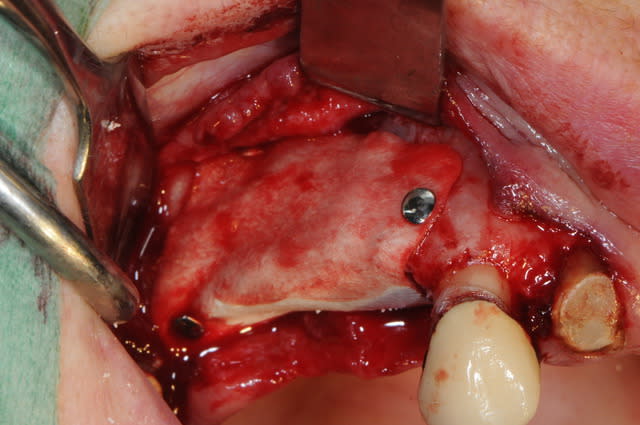

14 était fracturée et il y avait une infection +++ au niveau de la 15 avec perte de la table vestibulaire.

j'ai mis du bioos et membrane collagène AT résorbable fixée par trois pins.

le port de la prothèse est contre-indiqué pendant 2 mois ou alors avec un sérieux évidement de l'intrados.

elle a eu le plus dure. la pose des implants plus tard,ça sera du gâteau.

ceux sont les pins de chez FRIOS (densply). de tous ceux que j'ai utilisé, ceux sont finalement les seuls qui soit assez solides et rétentifs.

il y a aussi les membranes titanes..

si tu en veux n'achètes que l'applicateur droit ça suffit pour tout faire.